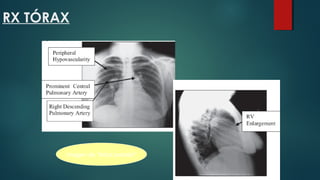

RX TÓRAX

Imagen de "árbol podado"

RX TÓRAX Imagen de"árbol podado"